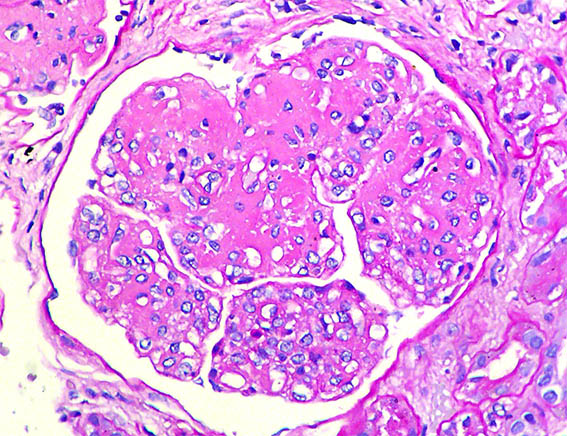

A 33-year-old man presented with pedal edema, persistent proteinuria and hypertension. Her past and family histories were unremarkable. Her blood pressure was 160/100 mm Hg. Physical examination revealed pedal and facial edema, without other alterations. Laboratory tests showed proteinuria of 4.7g/24 h, serum creatinine 1,0 mg/dL, microhematuria, normal serum complement levels, ANA negative; HIV, hepatitis B and C viral infections were negative. Ultrasound of the abdomen showed normal sized kidneys.

Kidney biopsy was performed. Look at the images.

Figure 2. PAS, X400.